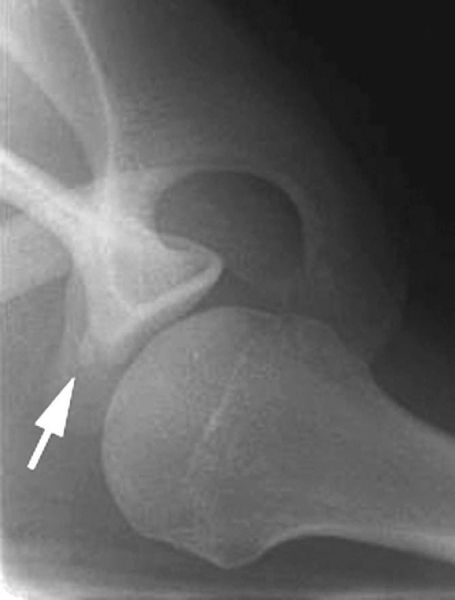

| • | A standard anteroposterior view with the arm in slight internal rotation is used to identify fractures of the greater tuberosity and Hill-Sachs lesions ( Fig. 3-1 ). |

| • | The West Point axillary view can be used to assess glenoid rim fractures (bony Bankart lesion; Fig. 3-2 ). |

Figure 3-2 |